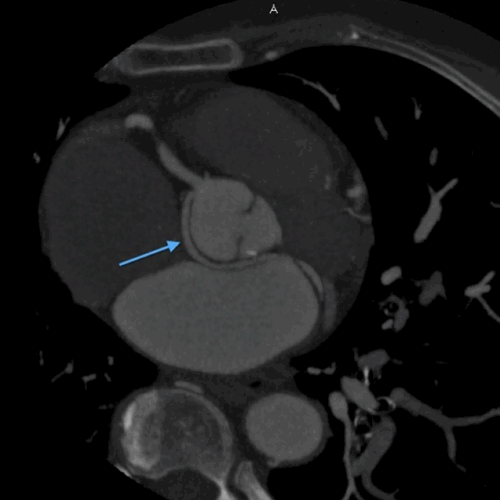

Case 1- Coronary anomaly- LCX FROM RCA

On MDCT angiography, left coronary artery was seen to arise from the left sinus of valsalva which further coursed along the anterior interventricular groove as LAD. RCA was seen to be arising from anterior aortic sinus with its normal course along right atrio-ventricular (AV) groove.